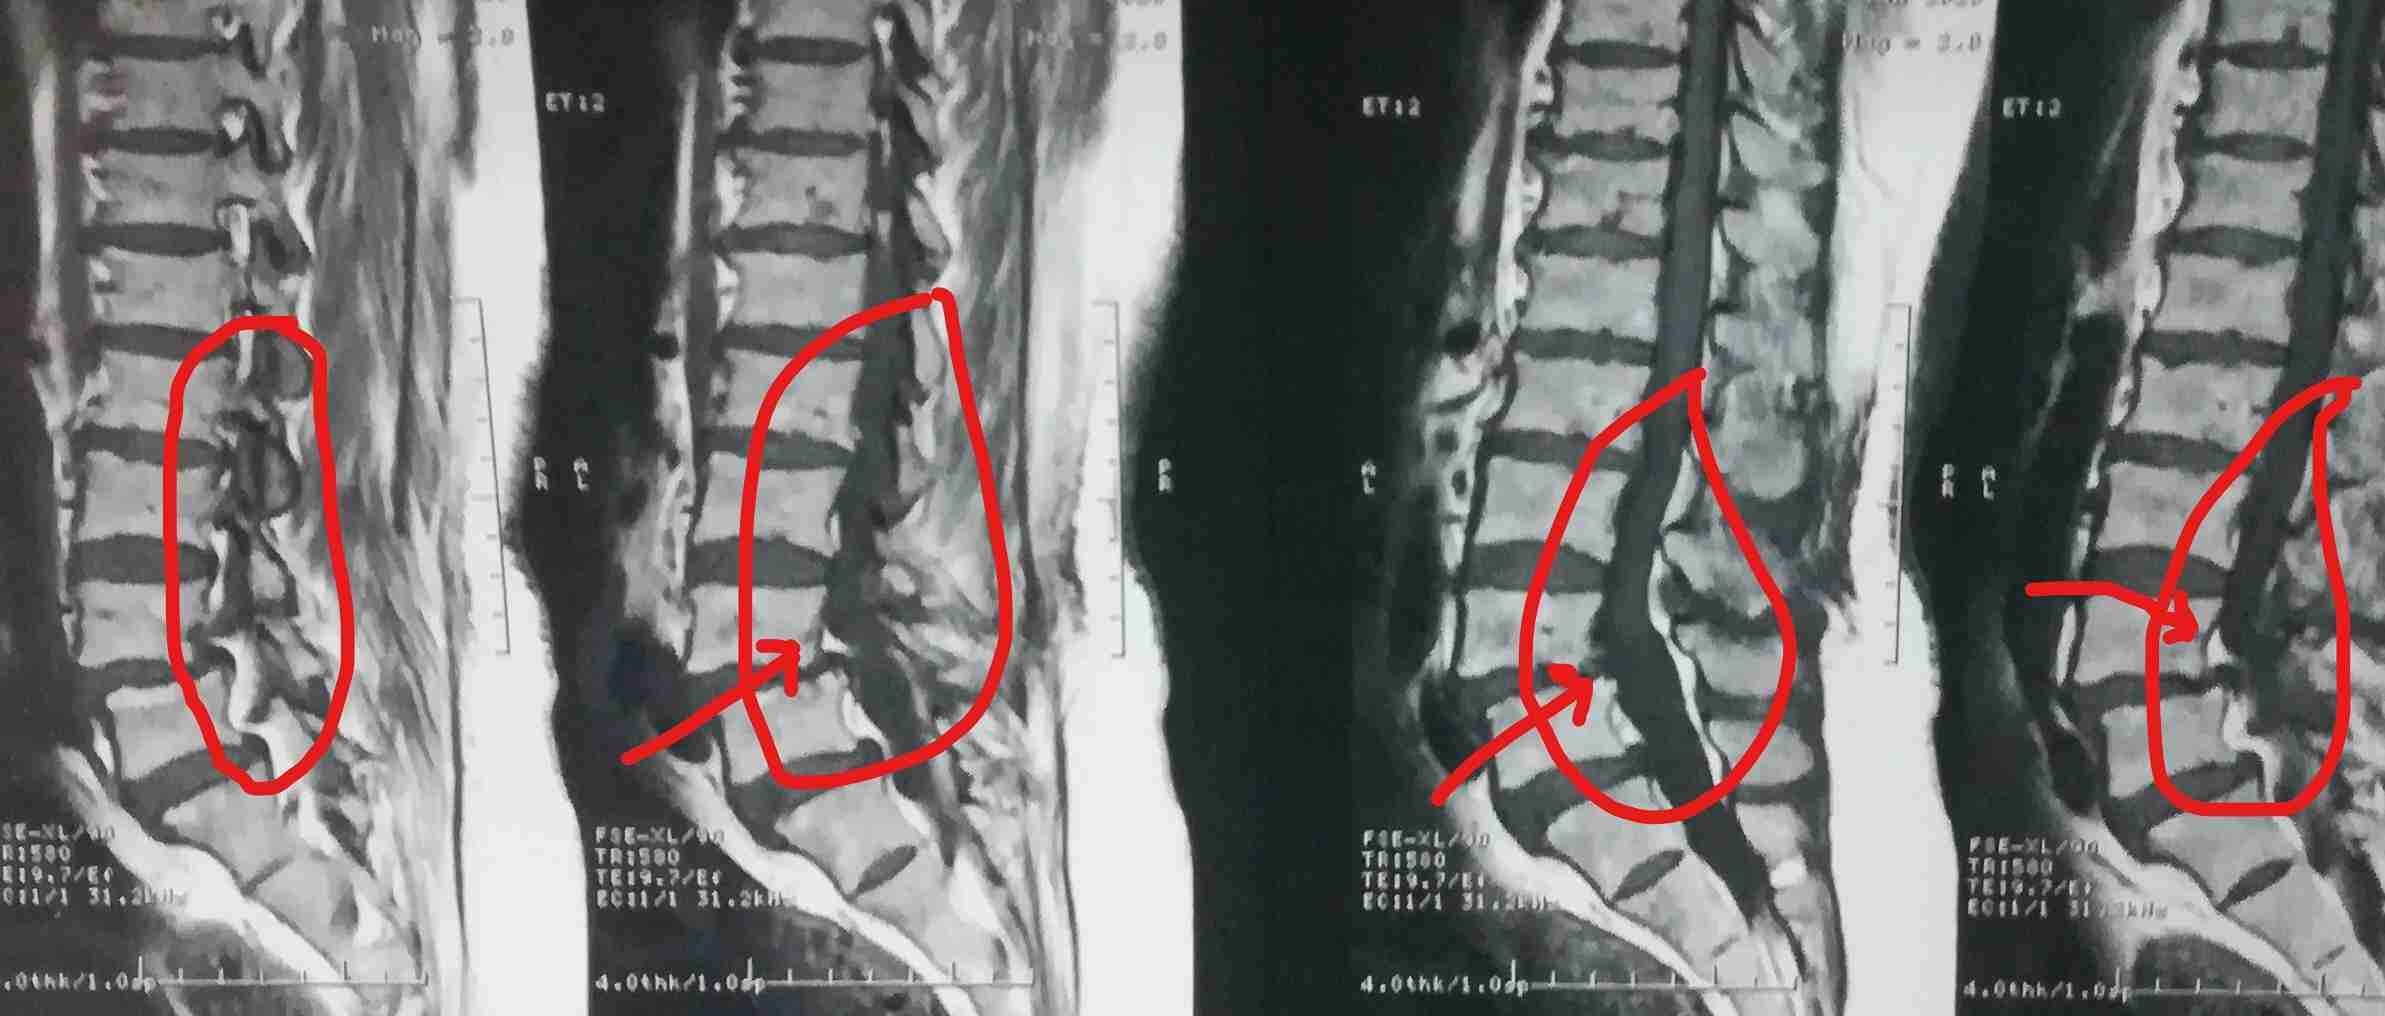

ضيق بالقناة العصبية القطنية مستويات متعددة مع تزحزح فقاري قبل وبعد الجراحة

multiple levels of lumbar nerve canal stenosis with spondylolisthesis before and after surgery

A successful surgery was performed to treat multi-level lumbar spinal stenosis accompanied by spondylolisthesis. This condition causes pressure on the nerves in the spinal column, leading to severe pain and difficulty in movement.

• Expanding the narrowed spinal canal at multiple levels

• Relieving pressure on spinal nerves